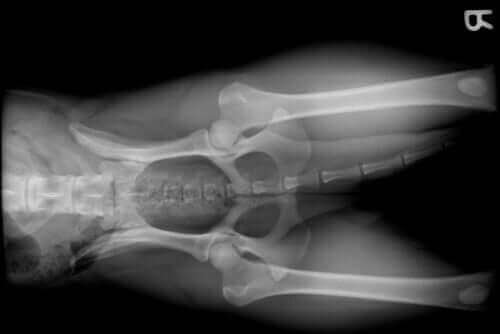

En af de mange grunde til, at en hund besøger dyrlægen, er forekomsten af lidelser i leddene. En hundeejer bemærker normalt dette problem hos deres hund på grund af forekomsten af halten og undertiden akut smerte.

Ledproblemer hos en hund kan forekomme af mange grunde, såsom:

- Racen. Visse hunderacer, såsom schæferhunde, udvikler normalt hofteledsdysplasi. På den anden side har racer som Golden Retriever, Rottweiler eller Doberman på grund af deres store størrelse og hurtige vækst en tendens til at lide af skulder- eller albueledsdysplasi.

- Fremskreden alder. Ligesom andre pattedyr, herunder mennesker, forekommer der, når hunde kommer i deres alderdom, forhold, der er knyttet til dette vitale stadie. Vi taler her om slidgigt hos hunde.

- Vækstproblemer. Perioden hvor en hund vokser er et vigtigt øjeblik, som i andre arter. Derfor kan fødevaremangel, hormonelle problemer eller race forårsage ledskader.

- Knoglebrud, der involverer et led.

- Korsbåndskade. På grund af overanstrengelse, overdreven træning eller en lille racestørrelse kan det forreste korsbånd briste. Dette vil resultere i alvorlige ledproblemer.

- Fedme. Ud over at reducere dit kæledyrs livskvalitet kraftigt forårsager fedme blandt andet overbelastning af led. Dette kan forårsage alvorlige problemer.

- Slidgigt.

- Leddegigt.